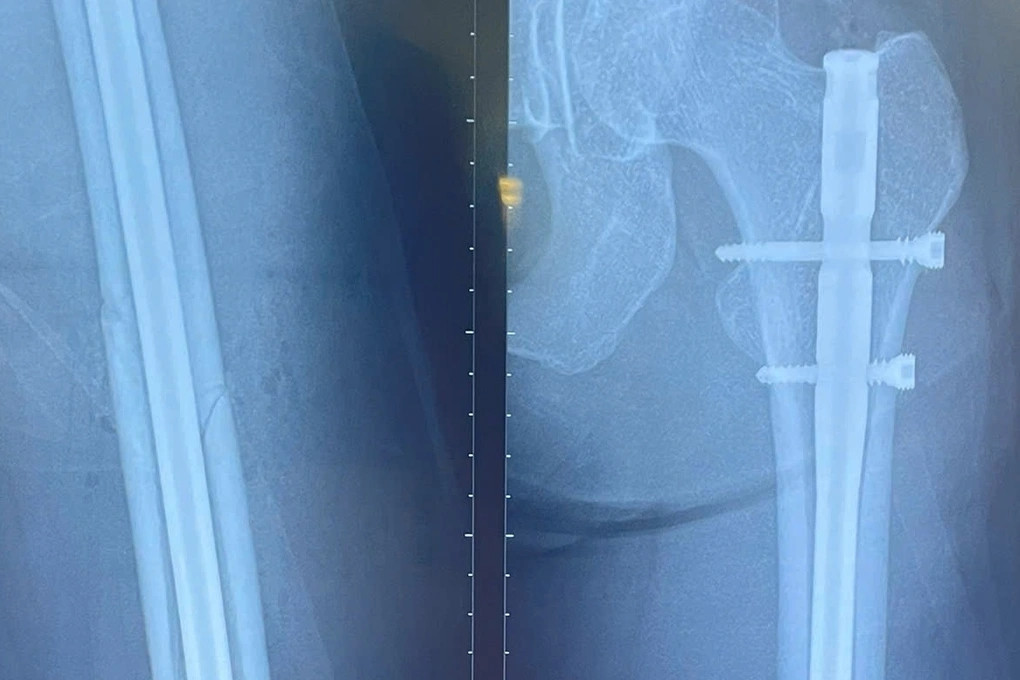

Nữ người mẫu cao 1m78 ở TPHCM gãy xương đùi trên sân pickleball

Nữ người mẫu 30 tuổi bất ngờ gặp tai nạn gãy xương đùi trên sân chơi pickleball tại TPHCM. Với chiều cao 1m78, đường gãy tét dọc xuống theo xương đùi trái nên ca mổ khó khăn hơn.